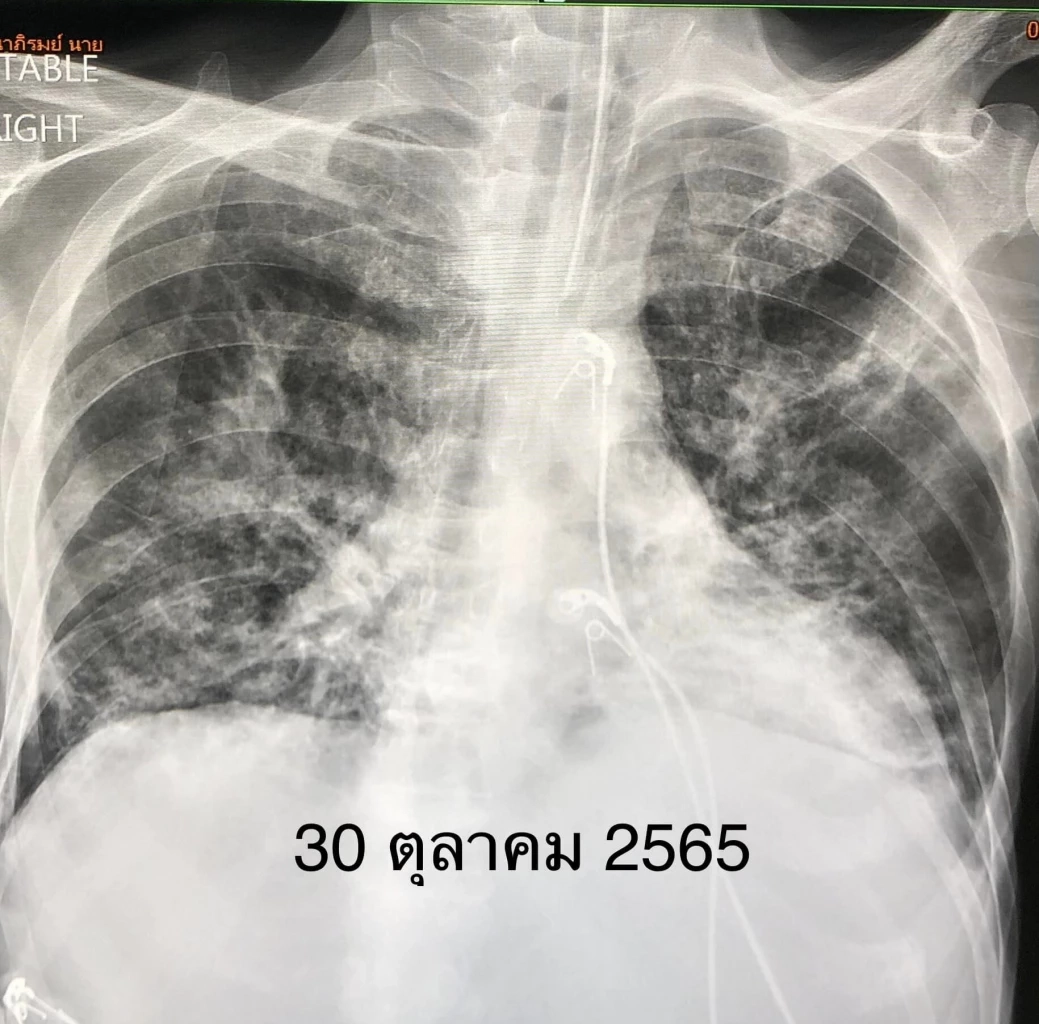

แต่หลังจากการรักษา คนไข้อาการดีขึ้นช้าๆ ความดันดีขึ้น ไข้ลง เหนื่อยลดลง ในที่สุดถอดเครื่องหายใจได้วันที่ 4 พ.ย. 2565 แต่ยังต้องใช้ออกซิเจนเสียบจมูก ได้ยาฉีดเรมเดซิเวียร์และสเตียรอยด์ครบ 10 วัน

วันที่ 9 พ.ย. ตรวจ ATK ซ้ำให้ผลลบ ระดับออกซิเจนปลายนิ้วขึ้นมา 96% เอกซเรย์ปอดดีขึ้นช้าๆ (ดูรูป)

วันที่ 16 พ.ย.คนไข้ดีขึ้นมาก ไม่มีไข้ ไม่เหนื่อย หมออนุญาตให้กลับบ้านได้ นอนรพ.ทั้งหมด 20 วัน"